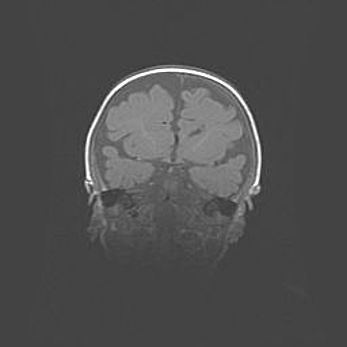

Открытая гидроцефалия.

Возраст: 9 месяцев 12 дней

Вес: 6800 г

Пол: мужской

Окружность головы: 41,5 см

Срок гестации: 28 недель

Гидроцефалия головного мозга у новорожденных имеет характерный признак: опережающий рост окружности головы приводит к визуально хорошо определяемой гидроцефальной форме сильно увеличенного в объёме черепа. Детские неврологи определяют следующие симптомы гидроцефалии у грудничков: выбухающий напряжённый родничок, частое запрокидывание головы, смещение глазных яблок к низу.